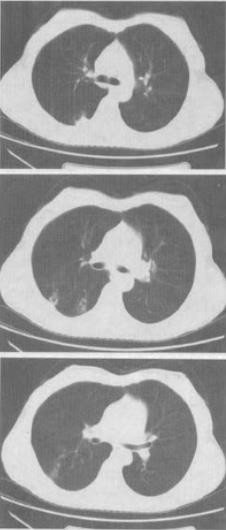

- 单项选择题 女,40岁,间断咯血1周,低热,行胸部CT扫描如图,最可能的诊断是()。

A、肺结核

B、肺部感染

C、支气管扩张并感染

D、支气管囊肿并感染

E、肺脓肿

- A